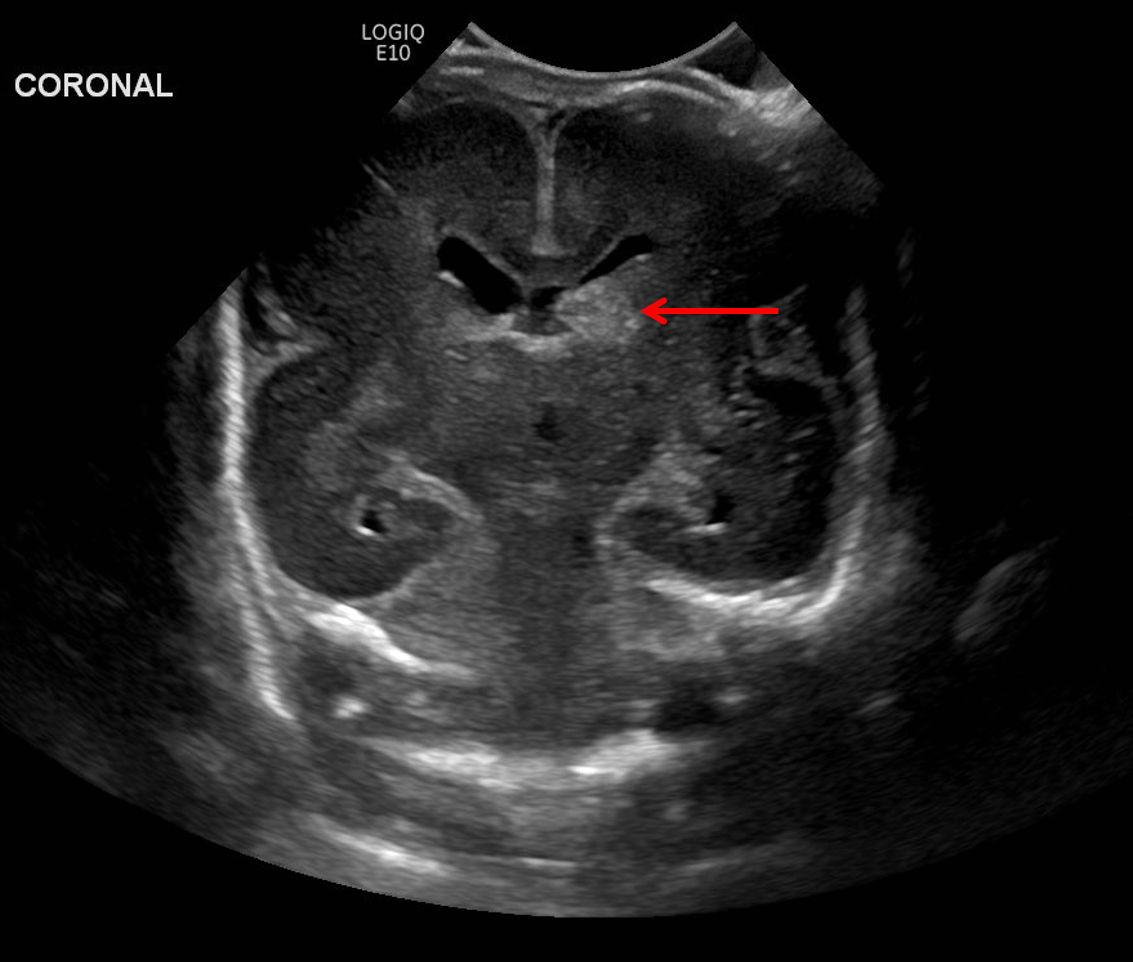

Age: 4 days (born at 24 weeks)

Sex: Male

Indication: Evaluate for germinal matrix hemorrhage

Grade 2 germinal matrix hemorrhage

Sample ReportLeft germinal matrix hemorrhage involving the caudothalamic groove and layering in the occipital horn of the left lateral ventricle without hydrocephalus (grade 2).

No abnormal brain parenchymal echogenicity or extra-axial collections.

Premature sulcation pattern.